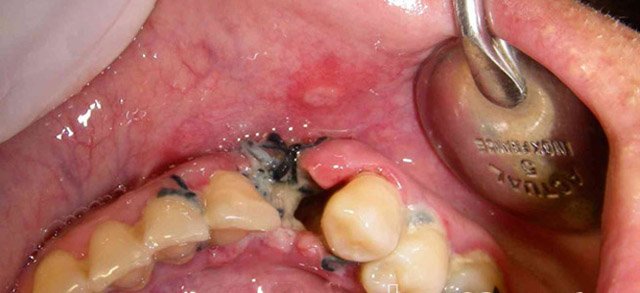

Видалення зуба — це не лише хірургічна процедура, а й значний стрес для вашого тіла. Після того як стоматолог видаляє зуб, на його місці залишається відкрита рана. Щоб ця рана могла загоїтися належним чином, їй потрібен абсолютний спокій. Їсти одразу після операції — все одно що поливати саджанець окропом: нічого хорошого з цього не вийде.

У першу чергу це стосується згустка крові, який утворюється на місці видаленого зуба. Цей згусток діє як природна “кришка”, яка захищає нерви та кістки від проникнення їжі, бактерій і допомагає уникнути інфекцій.